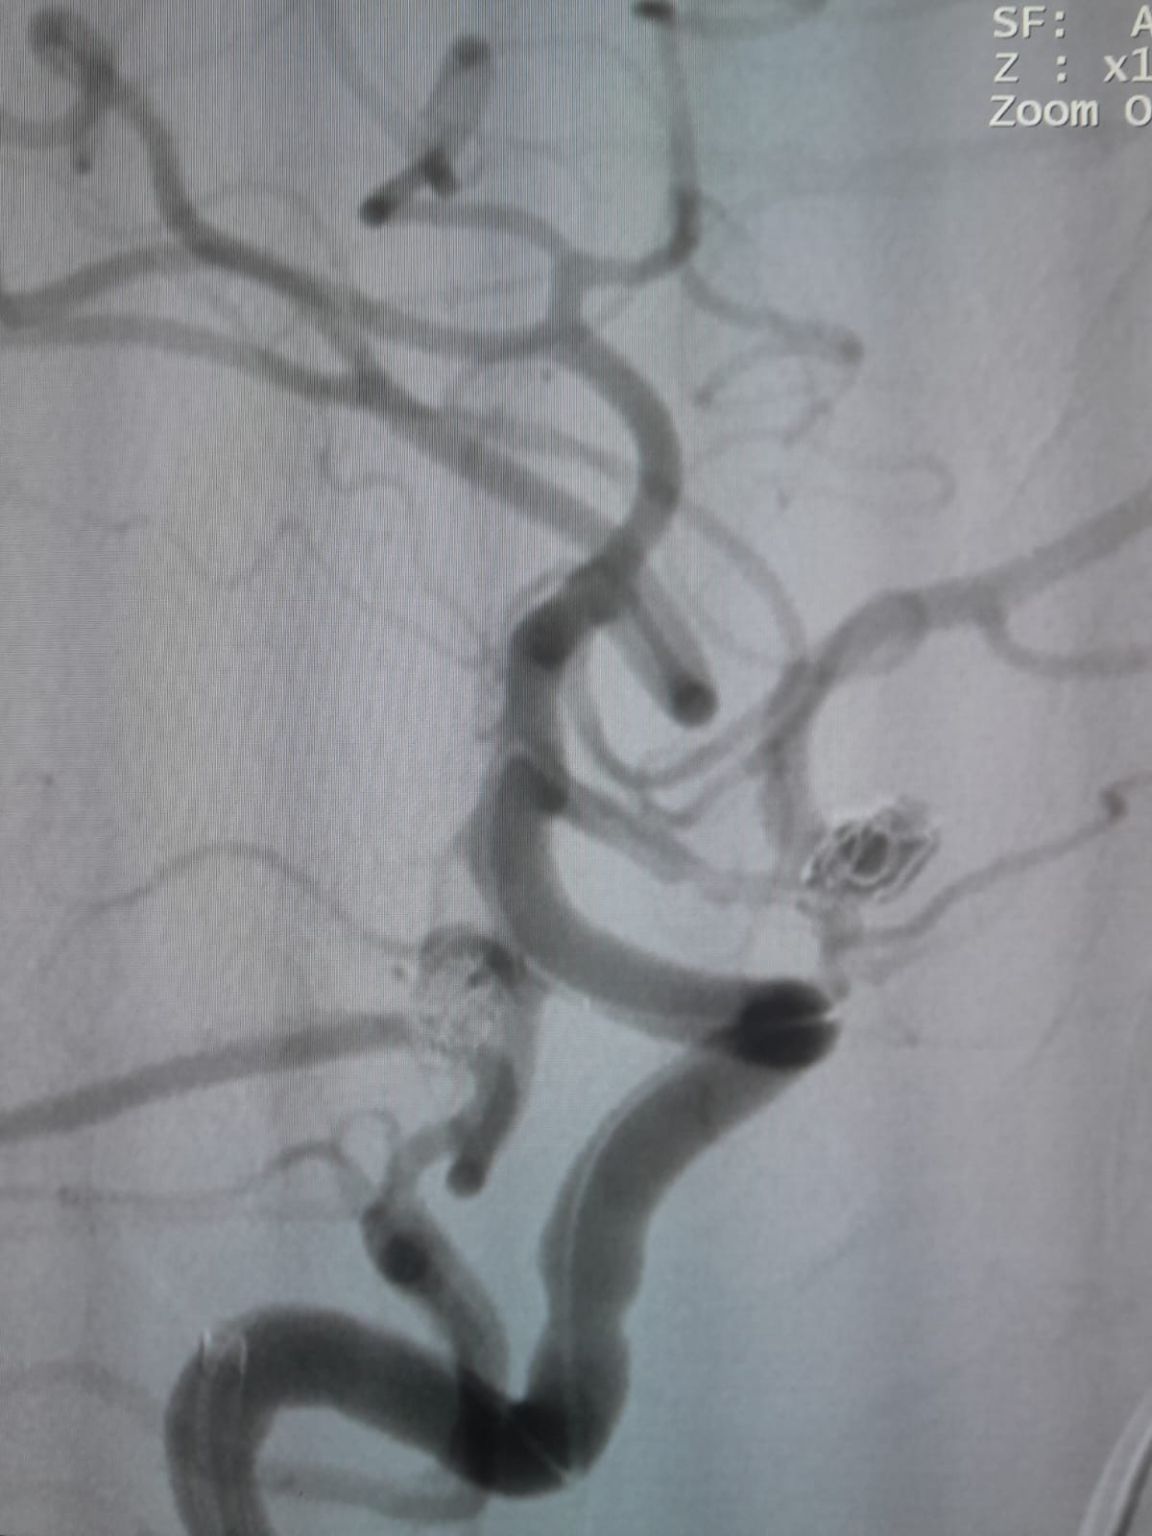

Al paziente è stato diagnosticato un aneurisma sacculare dell'arteria comunicante anteriore (AComA) appena scoperta e un aneurisma dell'arteria comunicante posteriore (PComA) che era stato precedentemente trattato con embolizzazione della bobina. L'imaging di follow-up ha rivelato il riempimento residuo dell'aneurisma PComA, che richiede un intervento aggiuntivo.

Aneurisma dell'arteria comunicante anteriore

È stato stabilito l'accesso vascolare e il team ha quindi navigato con successo nel Fepass®Microcatetere monouso (TJMC14) al sito di destinazione. L'embolizzazione è stata eseguita utilizzando tre Perdenser®Embolic Coil System (TJCST4.508-3D, TJCST0306-3D, TJCST0206-3D) implementato con Deromper®Controller di distacco della bobina (TJCDC).